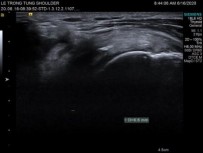

+ Siêu âm gân cơ trên gai:

Tư thế 1: tay xoay ngoài, khuỷu gấp 900, lòng bàn tay áp vào mông.

Kỹ thuật: vị trí đầu trên gân cơ nhị đầu là mốc giải phẫu, từ lát cắt qua đầu dài gân cơ nhị đầu, dịch đầu dò lên trên và ra sau để thăm khám gân cơ trên gai, riêng vị trí bám gân cần nghiêng nhẹ đầu dò để tránh ảnh giả.

Tư thế 2: tay đưa ra sau, mặt ngoài cẳng tay áp vào lưng, thao tác giống tư thế 1, nhưng ở tư thế 2 gân bị kéo căng hơn.

Hình 2.31. Hình ảnh siêu âm khảo sát cơ trên gai.

* Nguồn: ảnh chụp trong mổ của BN Trần Văn H, số bệnh án 19134370 và BN Chu Thị H, số bệnh án 20008219